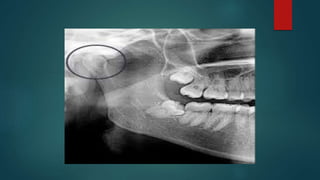

 Estudios de gabinete ( rx, ortopantomografía 2.- Una resonancia

nuclear magnética (RNM) maxilofacial, a nivel de las ATMs)

 En el estadio inicial el diagnóstico de la OA es difícil de separar de

otros desórdenes temporomandibulares. En el estadio intermedio

aparece dolor en la ATM y en el estadio terminal se encuentra una

reducción de los síntomas y una normalización de la función,

mientras que radiológicamente se observa una mayor

degeneración ósea y mayor frecuencia de perforación meniscal.

 Para que un paciente sea diagnosticado de O.A.

temporomandibular debe cumplir los siguientes criterios :

Crepitación a la auscultación de las ATM, grados de movilidad

limitados con desviación en la apertura hacia el lado afecto y

debe existir una evidencia radiográfica de cambios óseos

estructurales.